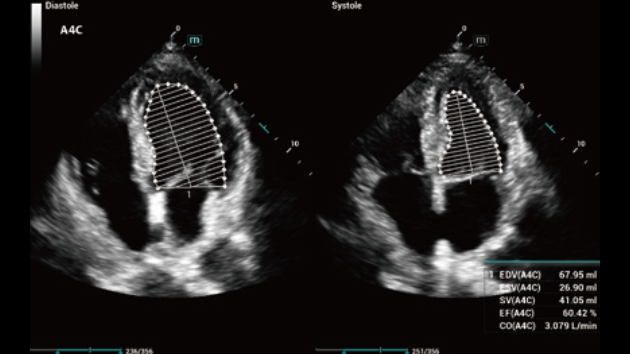

No matter your routine is in hospitals, clinics, or you are honing skills in General Imaging applications, women's health care or cardiovascular specialties, you will find highly powerful tools available on this series to keep you stay ahead.

Comprehensive Imaging Solutions Powered by ZST+

The ZST+ platform is an extraordinary innovation, representing an ultrasound evolution. Transforming ultrasound metrics from conventional beam-forming to channel data based processing. It overcomes the traditional trade-off limitation among spatial resolution, temporal resolution and tissue uniformity, delivering exceptional image quality for infinite imaging solutions with non-stop improvements.